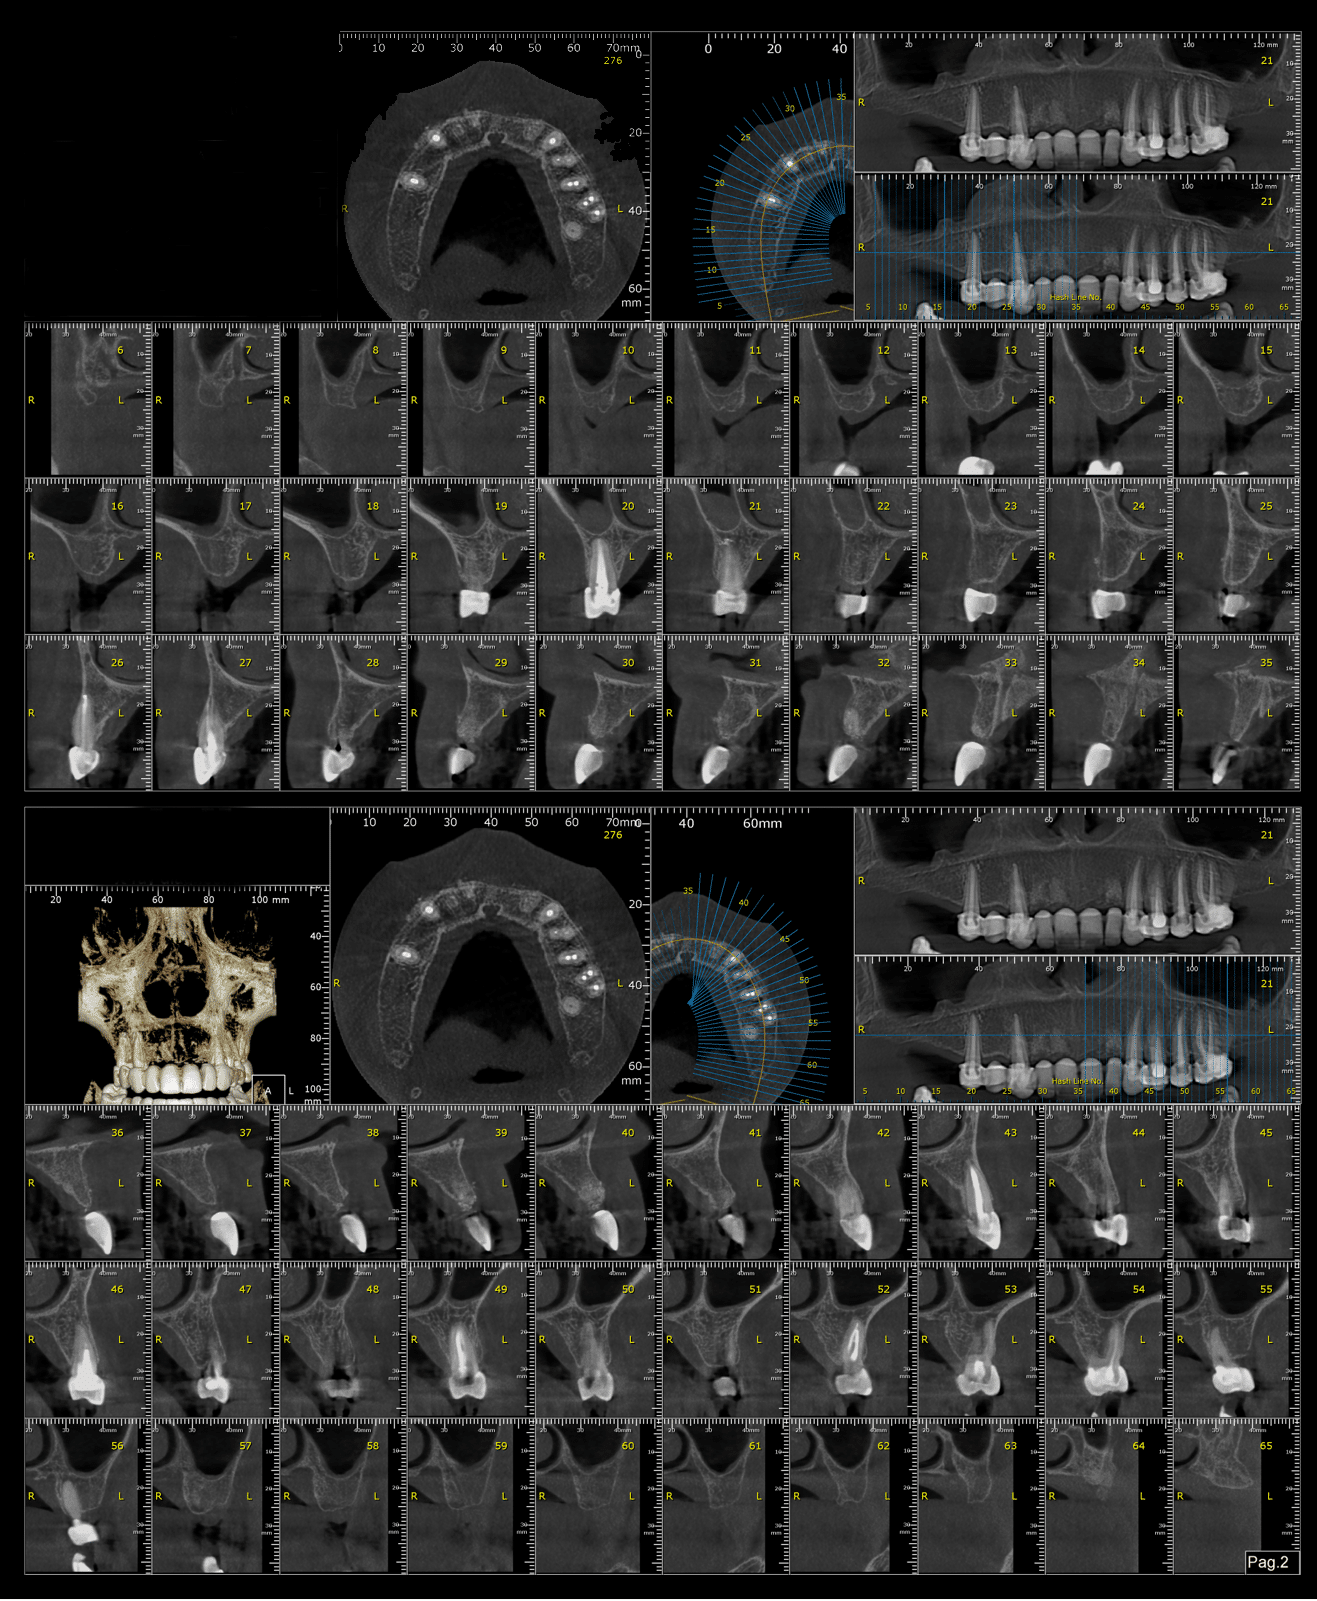

S-a realizat scanarea digitală a arcadelor și ocluzia pacientului, iar împreună cu tehnicianul radiolog de la DigiRay, Dr. Eliza Drăgan a efectuat în software-ul 3Shape suprapunerea fișierului .stl al amprentei digitale peste fișierul .dcm de la CBCT. Medicul a planificat individual poziția și axul de inserție al fiecărui implant.